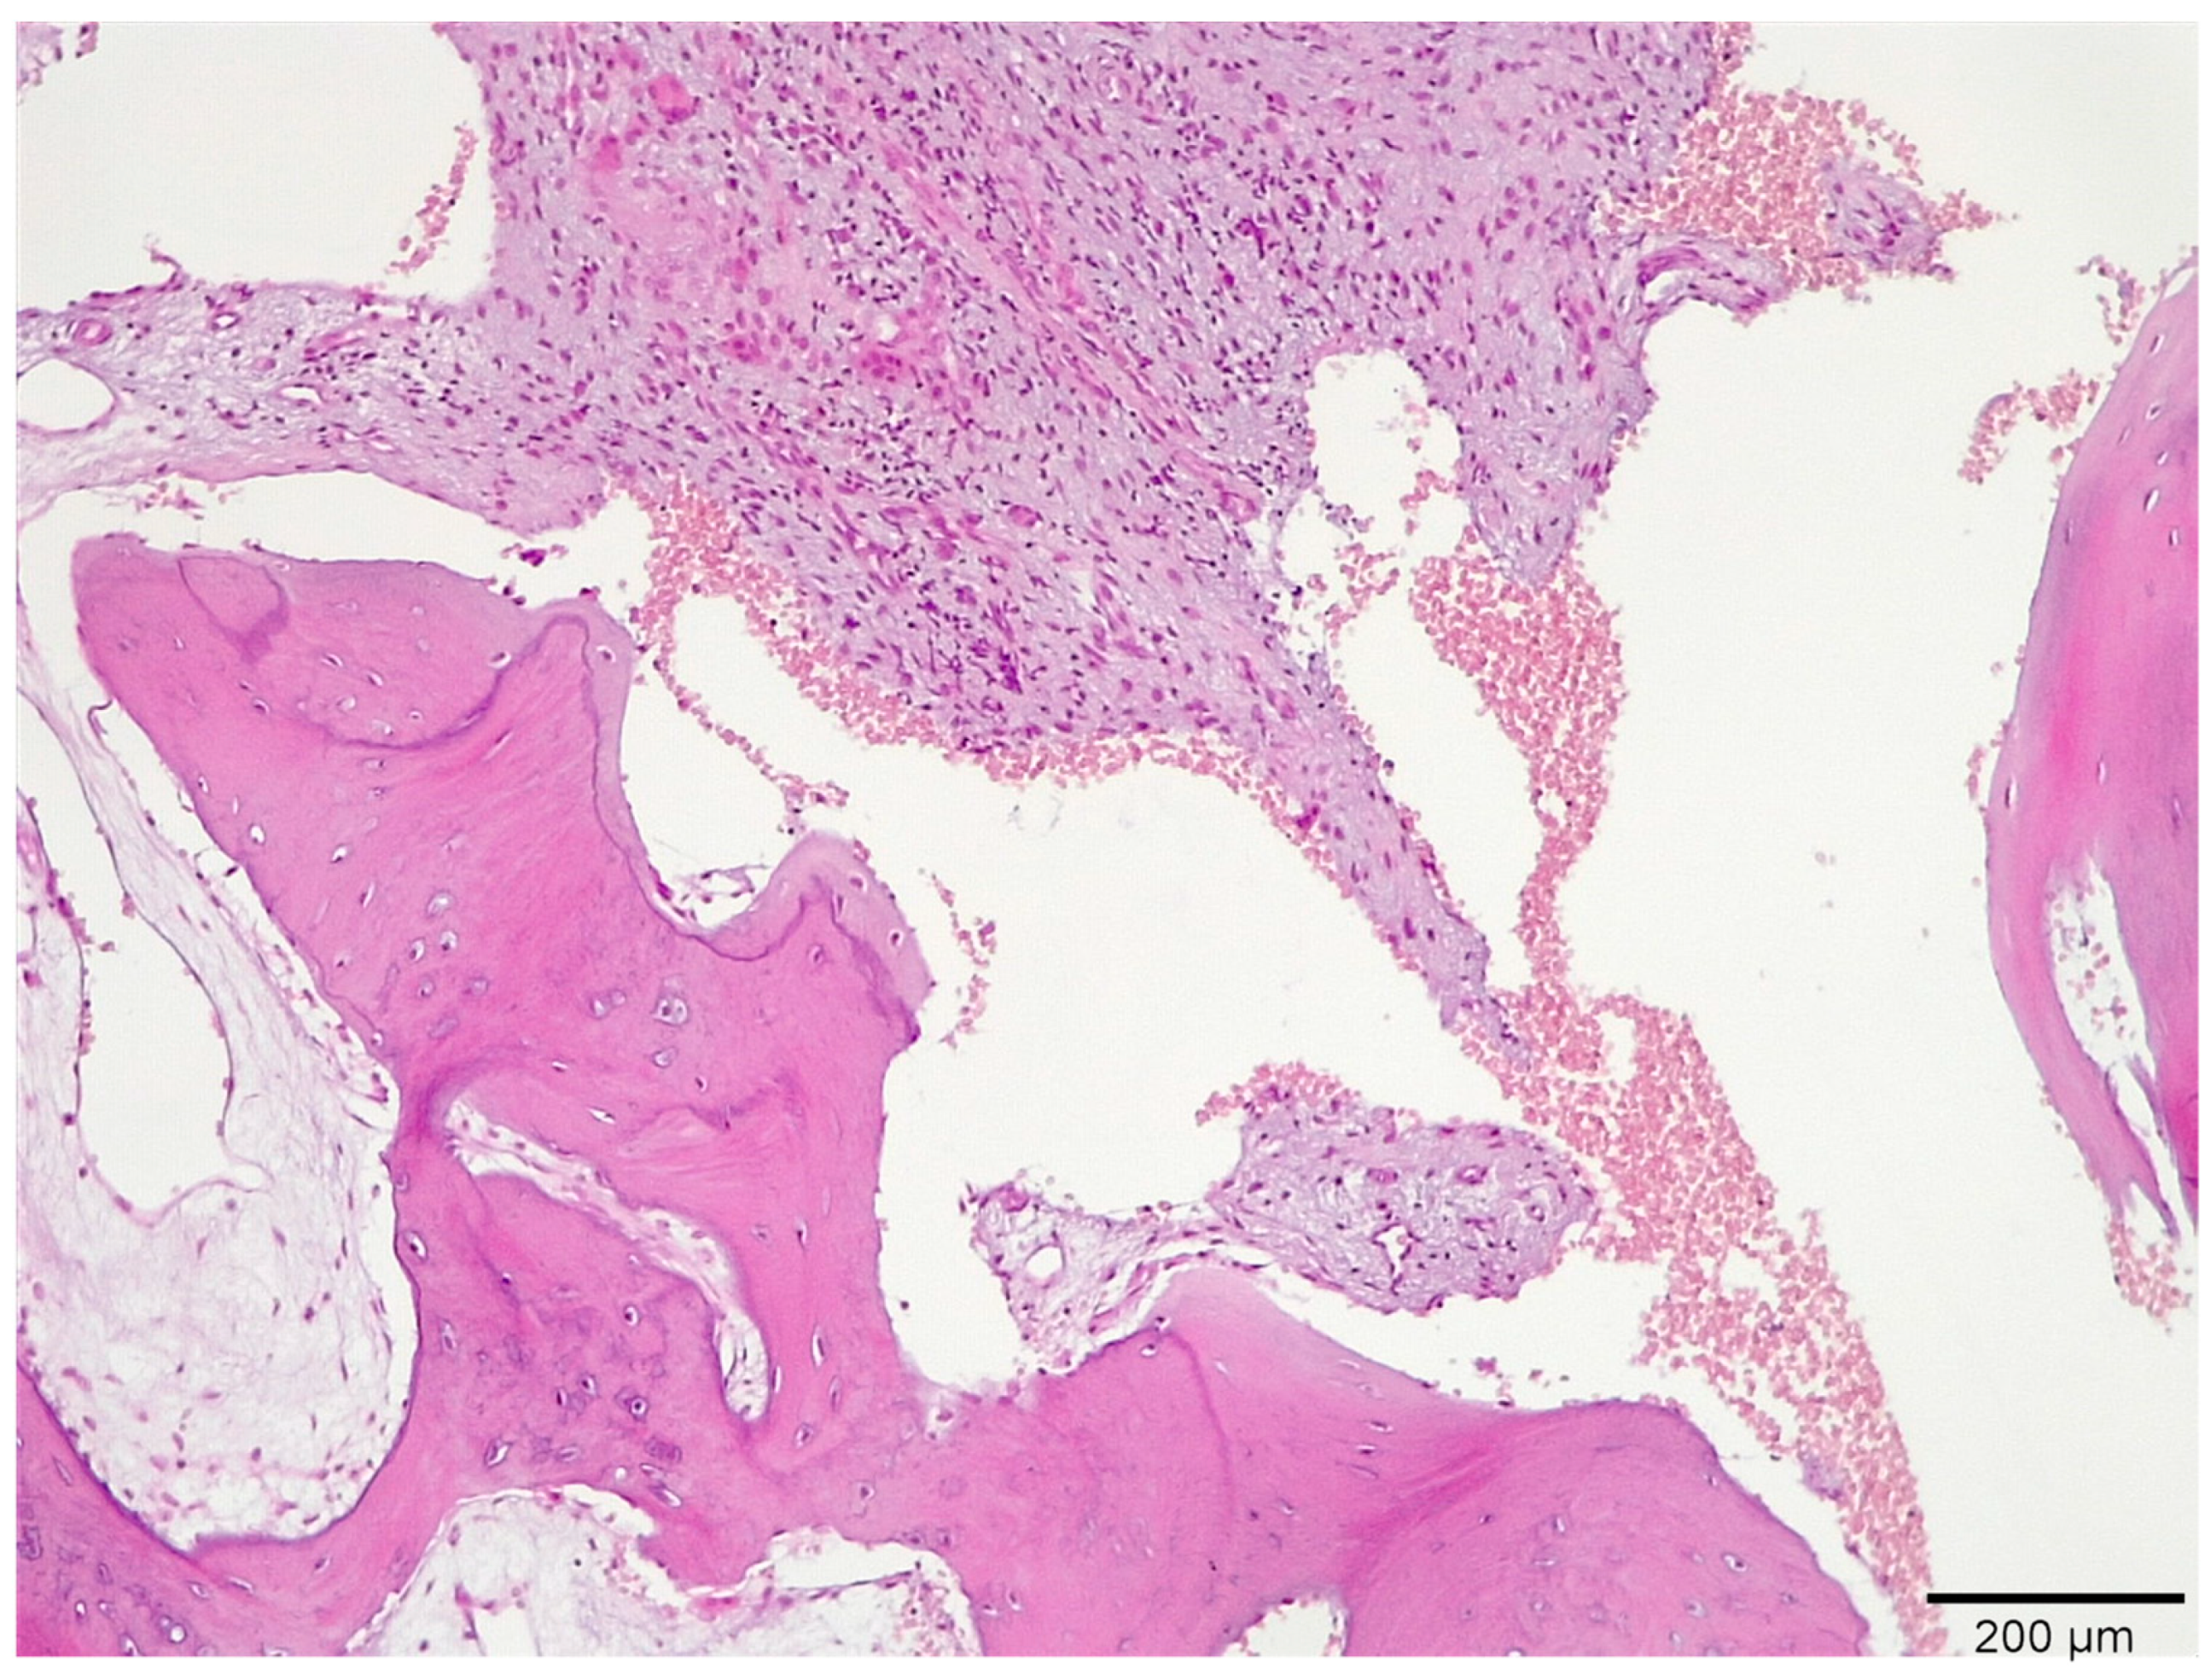

3.1. Histological Analysis Showed Signs of New Bone Formation at 60 Days

3.2. Histologic Data Obtained after Samples Analysis at 24 Months of Evaluation